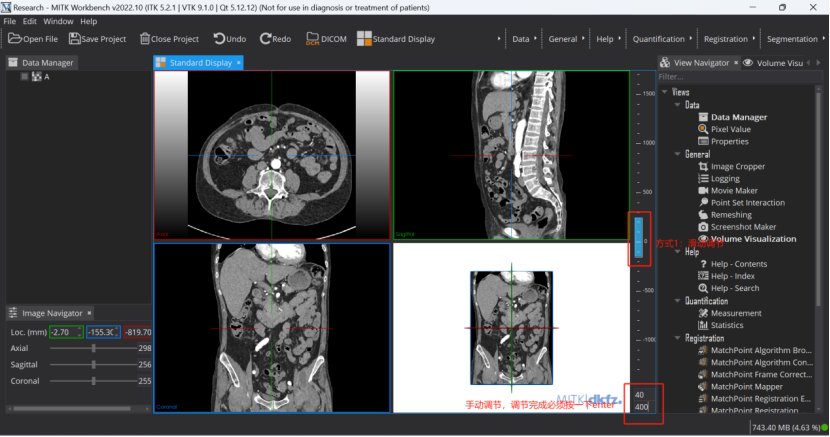

Step 2: 导入图像。即手动将亟待标注的”.nii.gz”文件拖动到下图区域

Step 3: 调节窗宽窗位。有两种方式,手动设置及滑动调节。如果标注肝肿瘤,我手动将窗宽窗位调节到[40-400]

Step 4 进入一个窗口进行标注: 进入单个视图画面更大,更有利于标注。